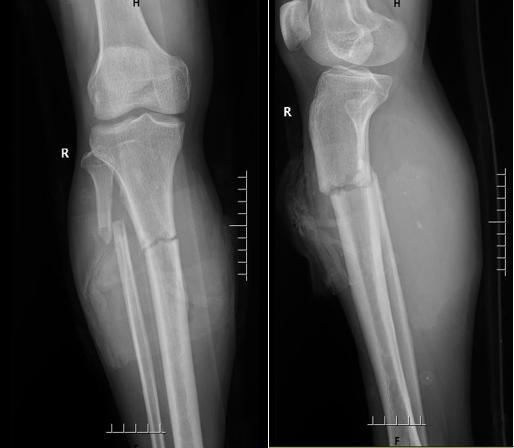

术后X线片检查

经过严密的讨论后 , 孙先生随即被推进手术室 , 手术由骨科副主任李泽主刀 , 冯兴义大夫配合完成 。 李泽副主任采用“清创+修复软组织+钢板巧妙外置固定骨折”的方式 , 在90分钟内顺利完成了手术 , 清创彻底、微创固定 , 将本例复杂开放性骨折手术完美完成 。